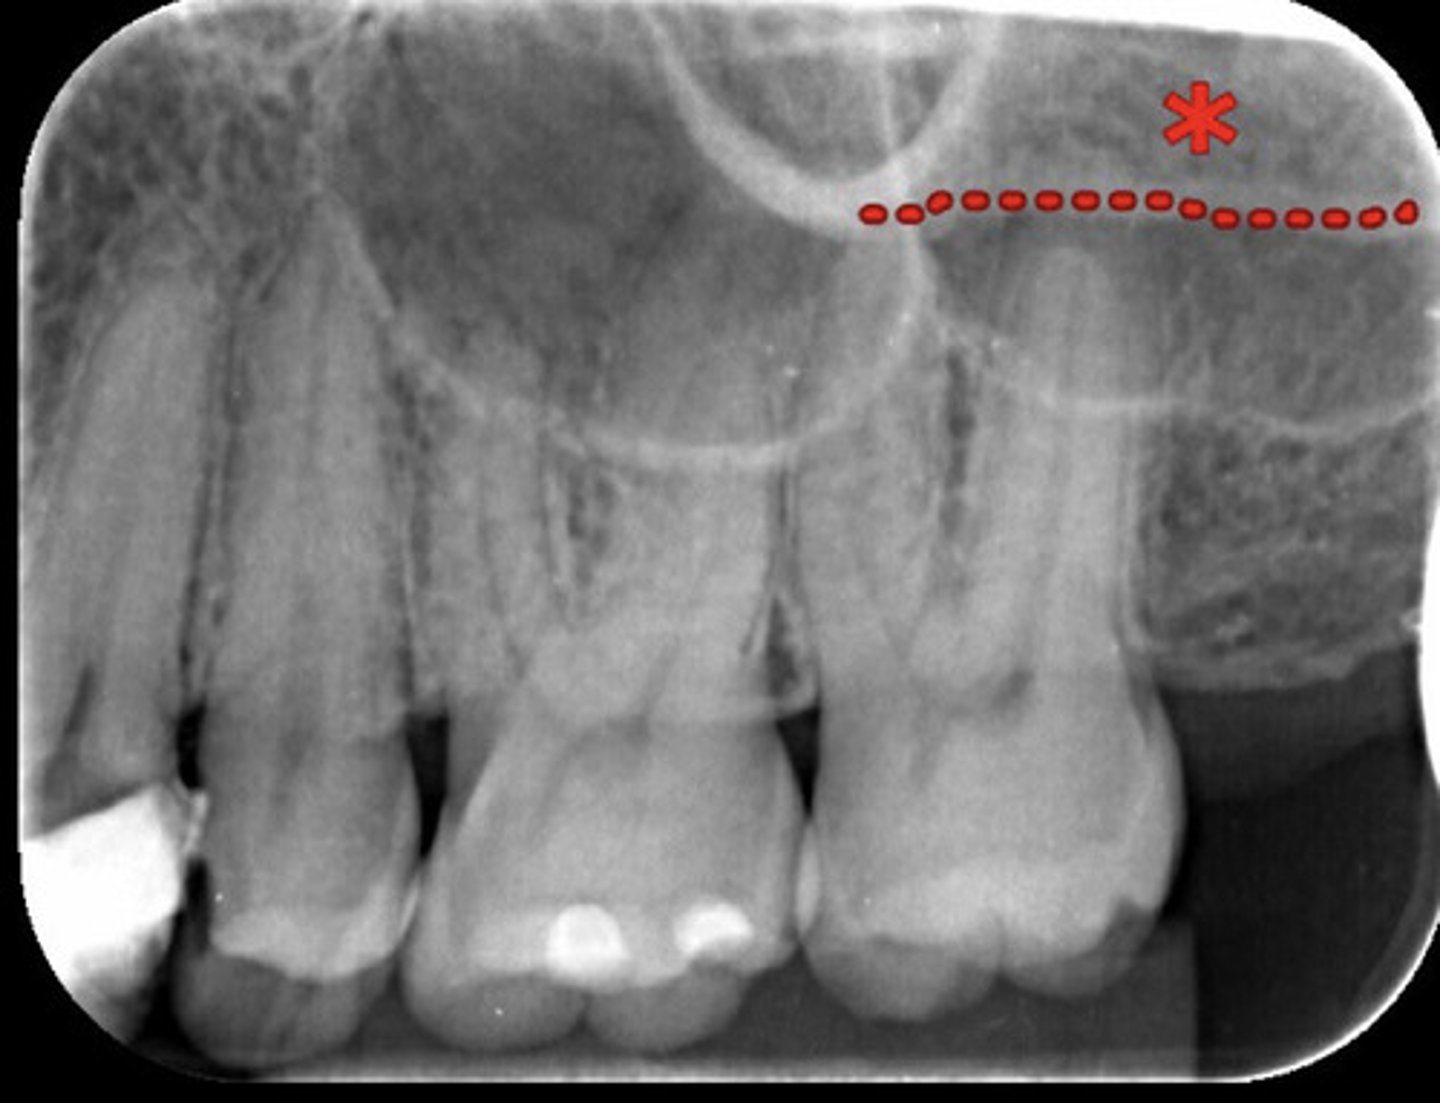

What is the red dotted line circling?

Maxillary sinus